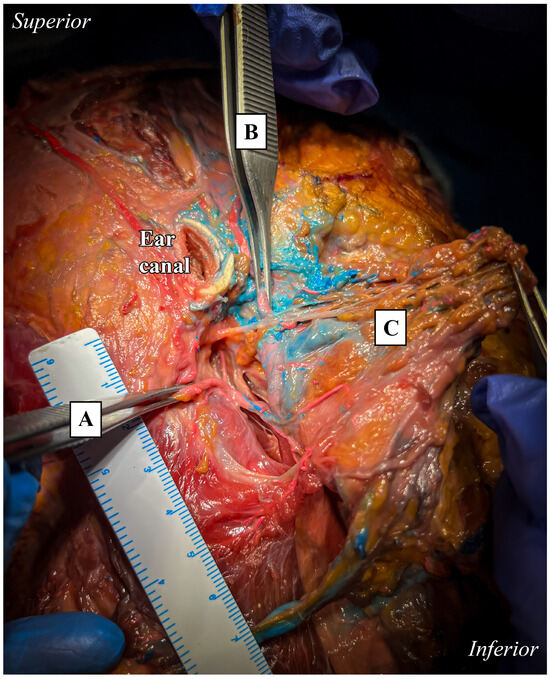

The anterior branch, identified as the frontal branch, followed an anterior course to the external auditory canal, while the posterior branch, identified as the parietal branch, ascended posteriorly. Their origin was approximately 4 cm below the lower margin of the external auditory canal cartilage, close to the lower border of the posterior belly of the digastric muscle. During its course, the anterior branch traversed the parapharyngeal space beneath the plane of the facial nerve and the stylomastoid artery (Figure 3). In this case, the relationship between the STA and the facial nerve highlights the importance of performing careful anatomical identification to prevent nerve injuries during surgical procedures.

Figure 3. Lateral view of the anatomical preparation of the infra-temporal and parotid regions. Emergence of anterior (middle clamp, B) and posterior (left clamp, A) terminal branches. Measurement of the distance from the inferior margin of the external auditory canal section of the emergence. Course of the anterior branch below the plane of the VII N.C. (C, lifting of superficial parotid). A ruler was used as the scale bar, providing an accurate reference for proportional measurements.